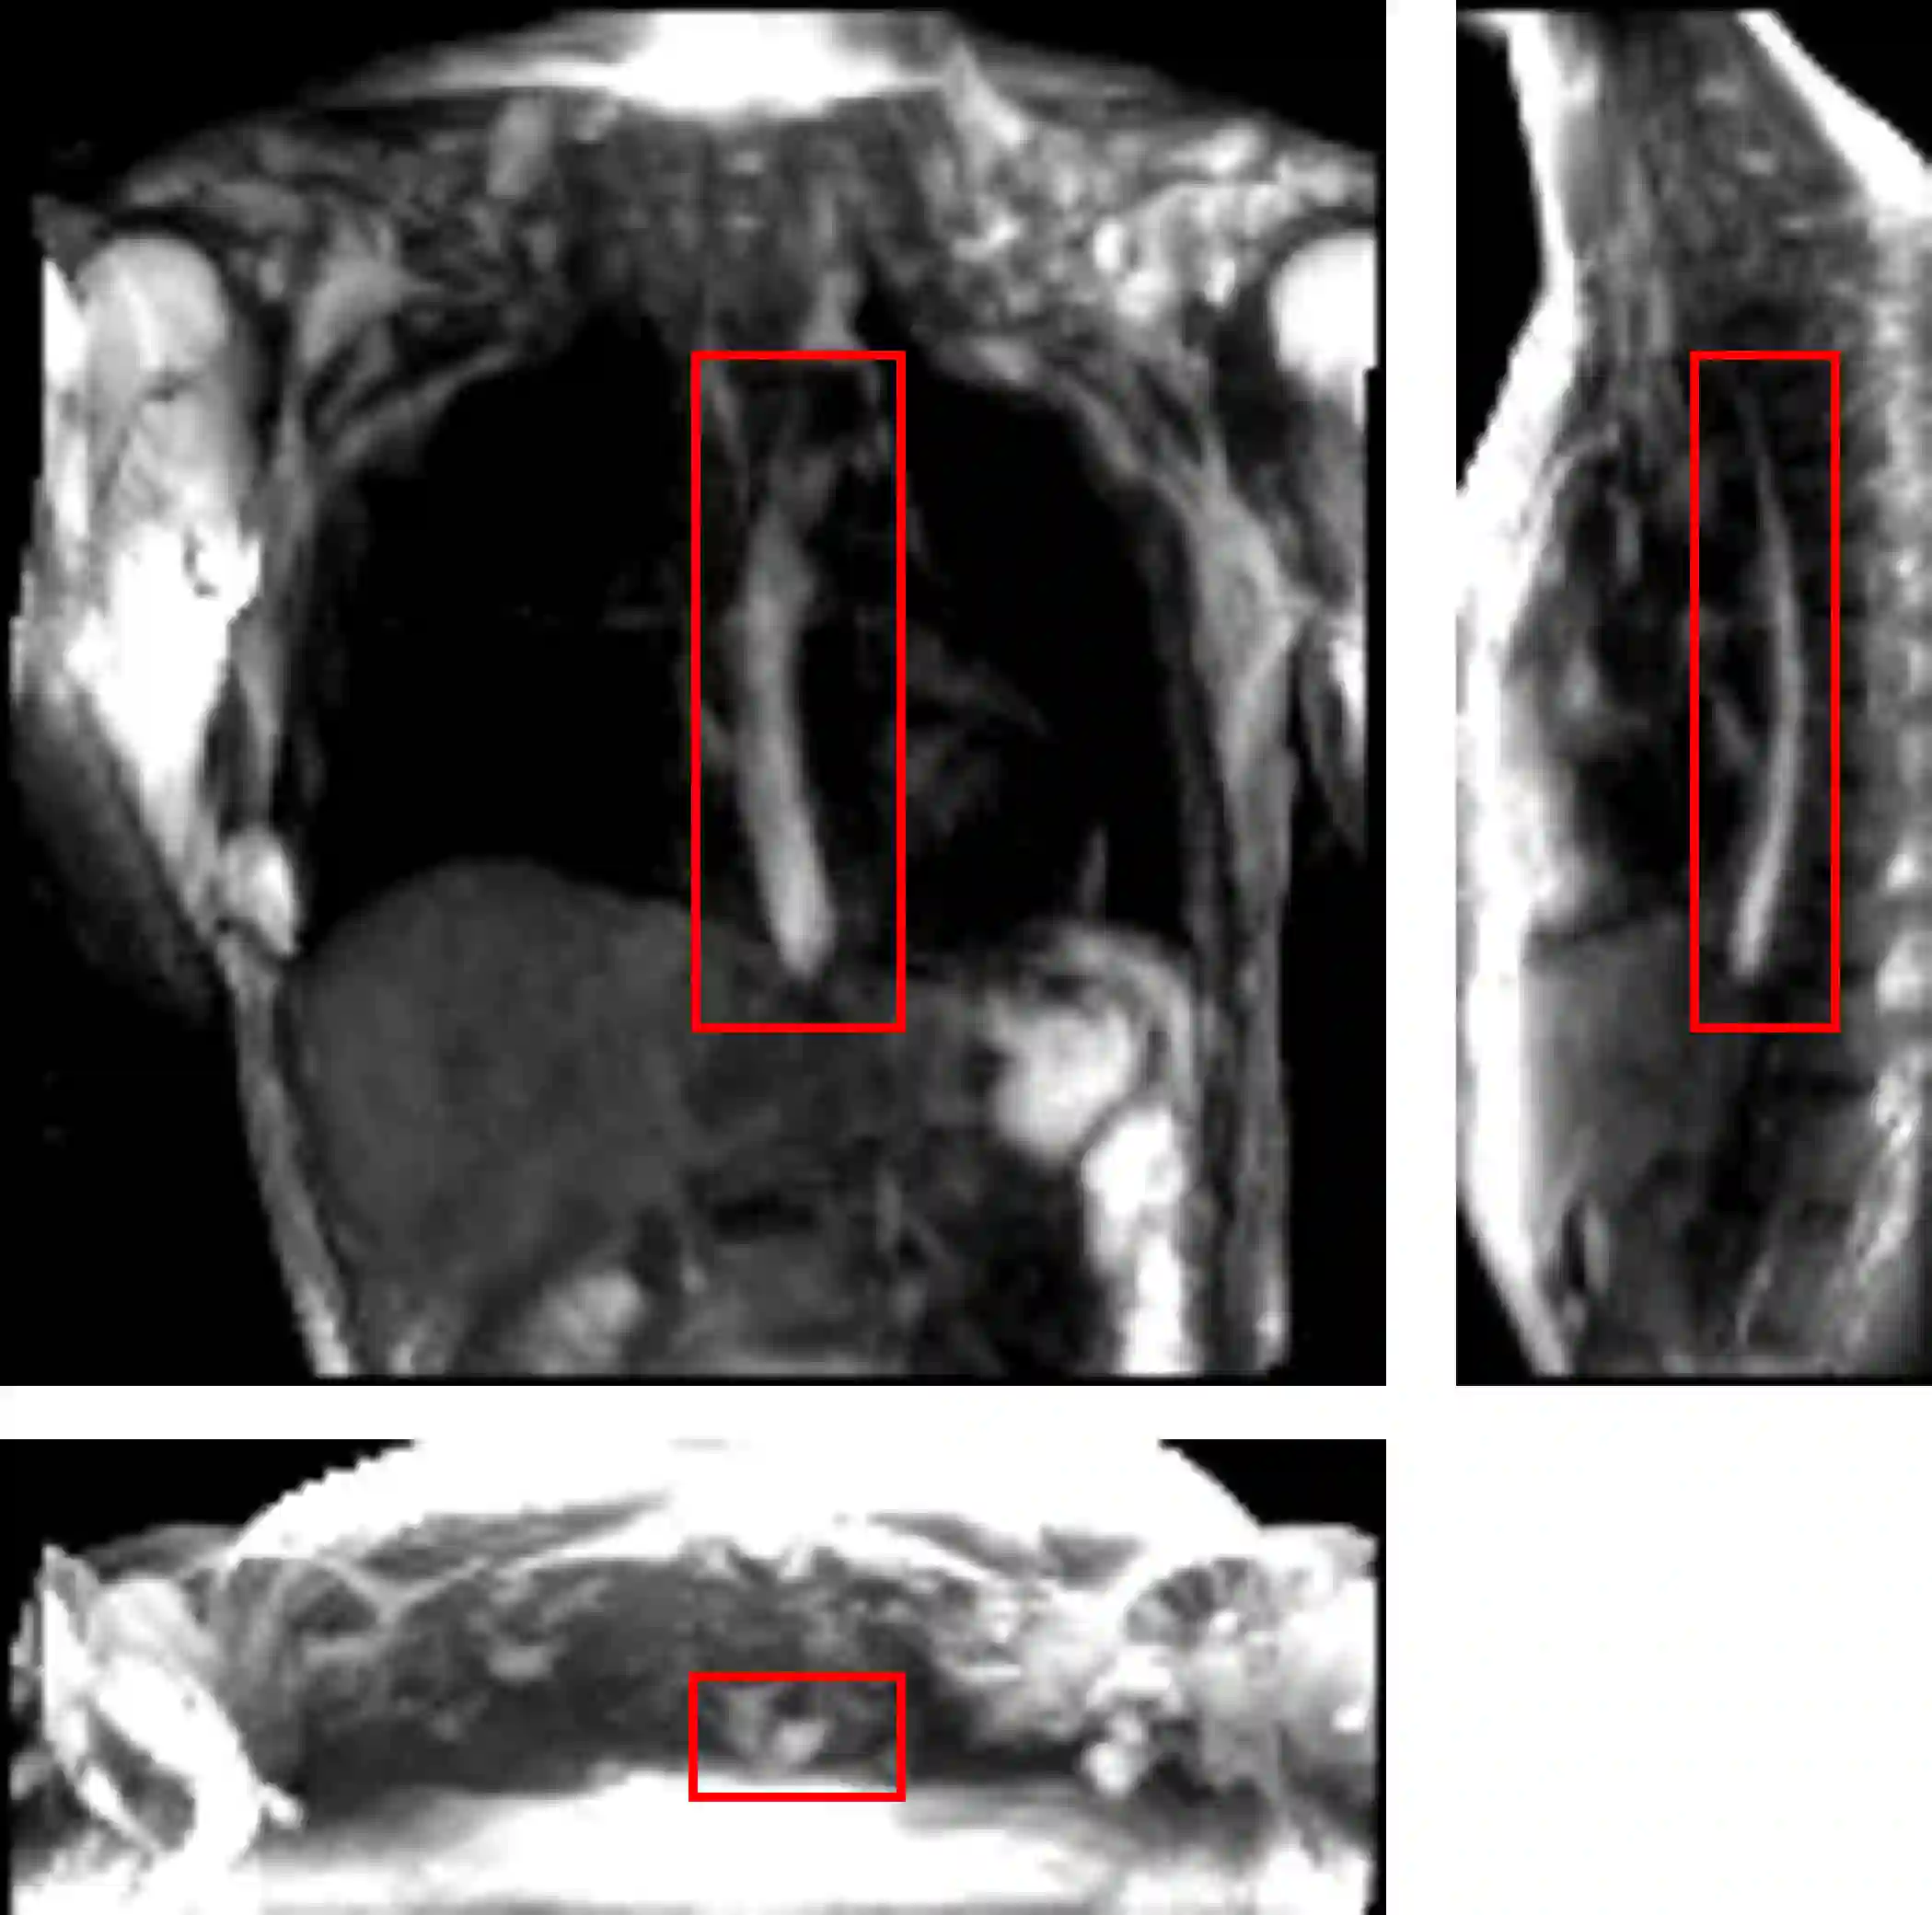

Dynamic magnetic resonance imaging (MRI) is a popular medical imaging technique to generate image sequences of the flow of a contrast material inside tissues and organs. However, its application to imaging bolus movement through the esophagus has only been demonstrated in few feasibility studies and is relatively unexplored. In this work, we present a computational framework called mechanics-informed MRI (MRI-MECH) that enhances that capability thereby increasing the applicability of dynamic MRI for diagnosing esophageal disorders. Pineapple juice was used as the swallowed contrast material for the dynamic MRI and the MRI image sequence was used as input to the MRI-MECH. The MRI-MECH modeled the esophagus as a flexible one-dimensional tube and the elastic tube walls followed a linear tube law. Flow through the esophagus was then governed by one-dimensional mass and momentum conservation equations. These equations were solved using a physics-informed neural network (PINN). The PINN minimized the difference between the measurements from the MRI and model predictions ensuring that the physics of the fluid flow problem was always followed. MRI-MECH calculated the fluid velocity and pressure during esophageal transit and estimated the mechanical health of the esophagus by calculating wall stiffness and active relaxation. Additionally, MRI-MECH predicted missing information about the lower esophageal sphincter during the emptying process, demonstrating its applicability to scenarios with missing data or poor image resolution. In addition to potentially improving clinical decisions based on quantitative estimates of the mechanical health of the esophagus, MRI-MECH can also be enhanced for application to other medical imaging modalities to enhance their functionality as well.